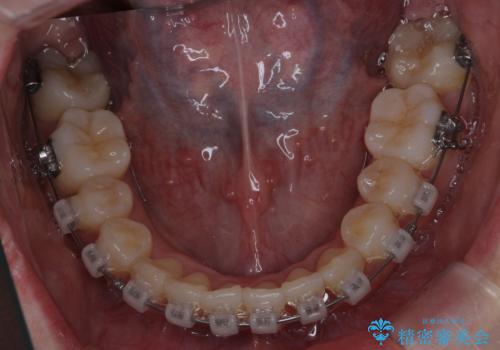

前歯は重度のがたつき、また奥歯はすれ違っていました。

治療は3年以上かかりそうと説明しましたが、2年台で終わらせることができました。

上下左右4本抜歯の可能性を説明していましたが、実際は上顎2本の小臼歯抜歯で済みました。

矯正用インプラントを使用して治療しています。

上下の顎の幅もあっておらず、成人でしたが手術なしで上あごを骨から広げる処置(急速拡大装置)を行いました。